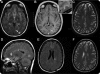

Objective: To describe a patient presenting with a clinically silent, incidentally found, and pathologically confirmed active demyelinating solitary cortical lesion showing MRI gadolinium contrast enhancement, in whom biopsy was performed before the radiographic appearance of disseminated white matter lesions.

Methods: Neurologic examination, MRI, CSF and serologic analyses, and brain biopsy were performed. Sections of formalin-fixed paraffin-embedded biopsied brain tissue were stained with histologic and immunohistochemical stains.

Results: Biopsy revealed an inflammatory subpial lesion containing lymphocytes and myelin-laden macrophages. Recurrent relapses with dissemination of MRI-typical white matter lesions characterized the subsequent course.

Conclusions: Our findings highlight that cortical demyelination occurs on a background of inflammation and suggest that the noninflammatory character of chronic cortical demyelination may relate to long intervals between lesion formation and autopsy. This case provides pathologic evidence of relapsing-remitting MS presenting with inflammatory cortical demyelination and emphasizes the importance of considering demyelinating disease in the differential diagnosis of patients presenting with a solitary cortical enhancing lesion.